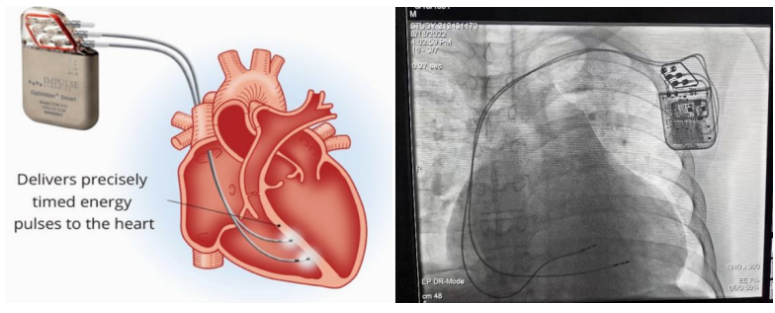

②心臟再同步治療

Cardiac Resynchronization Therapy,CRT

心臟再同步化治療,指雙心室起搏器,是通過(guò)雙心室同步起搏的方式,幫助心衰患者實(shí)現(xiàn)正常起搏的裝置。CRT包括一個(gè)口袋大小的脈沖發(fā)生器和三根電極導(dǎo)線,可被植入人體。通過(guò)監(jiān)測(cè)心律,在發(fā)現(xiàn)異常后,信號(hào)發(fā)生器發(fā)送電流脈沖,刺激心室重新同步,從而改善癥狀,提高患者的心臟泵血效率。目前有兩種類(lèi)型的CRT裝置:植入式心臟再同步治療起搏器(CRT-P)和植入式心臟再同步治療除顫器(CRT-D)。主要區(qū)別在于后者除了改善心臟收縮同步性外,還具備除顫功能,能及時(shí)處理危及生命的室性心律失常,避免猝死。

國(guó)內(nèi)研發(fā)企業(yè):無(wú)雙醫(yī)療、樂(lè)普醫(yī)療、先健科技、創(chuàng)領(lǐng)心律、秦明醫(yī)學(xué)等